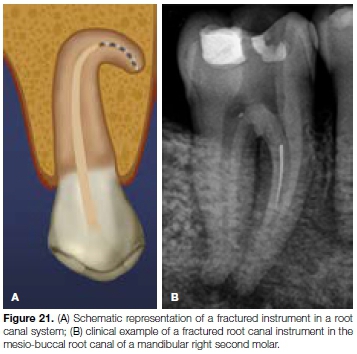

A common problem with the use of rotary files is the potential risk of separation or breakage within the canals.29 In most clinical situations, the breakage of the instrument occurs in the apical third of the canal and the remaining portion is often difficult or impossible to remove.30,31 Attempts at removal may even result in other procedural errors like perforation. The fragment that is left behind blocks the root canal system and results in inadequate cleaning, shaping and sealing (Figure 21A and 21B).32

Fracture of rotary instruments can occur because of tor-sional overload33, or fatigue through flexure.34 The torsio-nal fracture occurs when the tip or any other part of the instrument binds to the canal walls while the hand piece keeps turning. When this binding occurs and the elastic limit of the metal is exceeded, fracture of the instrument is inevitable.

This type of fracture has been associated with the application of excessive apical force during instrumentation. Fracture resulting from flexural fatigue occurs when an instrument that has already been weakened by metal fatigue is placed under stress.

The instrument does not bind to the canal wall but rotates freely until the fracture occurs at the point of maximum flexure.33 This type of failure is believed to be an important factor in the fracture of nickel-titanium (NiTi) rotary instruments in clinical usage, and might result from their use in curved canals.30 Various factors have been associated with the fracture of rotary instruments: rotational speed and angle and radius of curvature,30 instrument design and instrumentation technique35, torque36, and operator experience.37